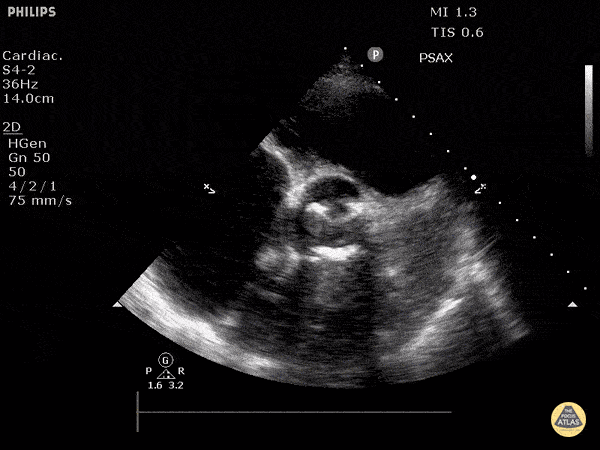

Valvulopathy - Aortic Valve Prosthesis (Short)

Justin Bowra MBBS, FACEM, CCPU Emergency Physician, RNSH et al. (with Dr. Orr)

https://www.thepocusatlas.com/valvulopathy